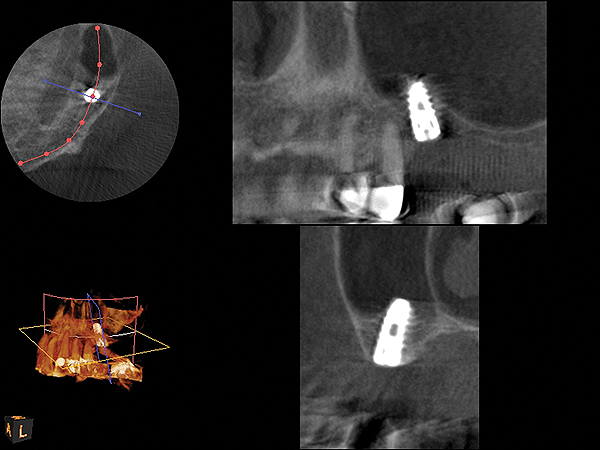

Fig 7. 4-month CBCT scan (Kodak 9000D) of implant No. 14.

Figure 7

Because the bone grafting materials used in this technique need physical stability during healing to support the raised membrane, there is a high probability that significant shrinkage of the graft will occur as it heals and matures if only non-demineralized material is used. For these reasons, a composite graft using calcium sulfate, DFDBA, and mineralized particulate bone is used. A 50:50 mixture by volume of mineralized bone grafting material and DFDBA is used, to which approximately 40% calcium sulfate by volume is added. A higher percentage of calcium sulfate is used relative to that described for composite grafting in other uses, because some of the calcium sulfate will wash out during bone packing. Another advantage to this composite graft is that it is not as radiopaque as a purely mineralized graft. This allows radiographic monitoring of the bone healing around the implant, which can be used to time abutment placement on the implant. This is demonstrated in Figure 4 and Figure 5, which are radiographs taken on the day of the initial surgery showing the radiographic appearance of the composite graft, implant, and graft, and in Figure 6, a 5-month postoperative radiograph with the abutment in place. The old floor of the sinus is indistinguishable from the area of new bone. Figure 7 shows a CBCT scan (Carestream Dental, www.carestreamdental.com) taken at 4 months with the old floor of the sinus indistinguishable from the new bone formed.

This patient was a 73-year-old man with only about 3.5 mm of native bone in the No. 3 site (Figure 20). The composite graft used here was a 50:50 mixture of DFDBA and deproteinized bovine bone mineral (Osteohealth, www.osteohealth.com) with approximately 40% calcium sulfate added. The implant was the same type and length as in Case 1 above. Figure 21 shows the area on the day of placement. In the CBCT scan on the day of placement (Figure 22), the native bone and bone graft were clearly discernable. However, the postoperative radiograph taken at 6.5 months (Figure 23) showed no marginal bone loss and a significantly denser appearance than when the graft was place. The membrane was raised about 7 mm to 8 mm. The final radiograph was taken after extraction of tooth No. 2 and after extraction of tooth No. 4 and immediate implant placement.